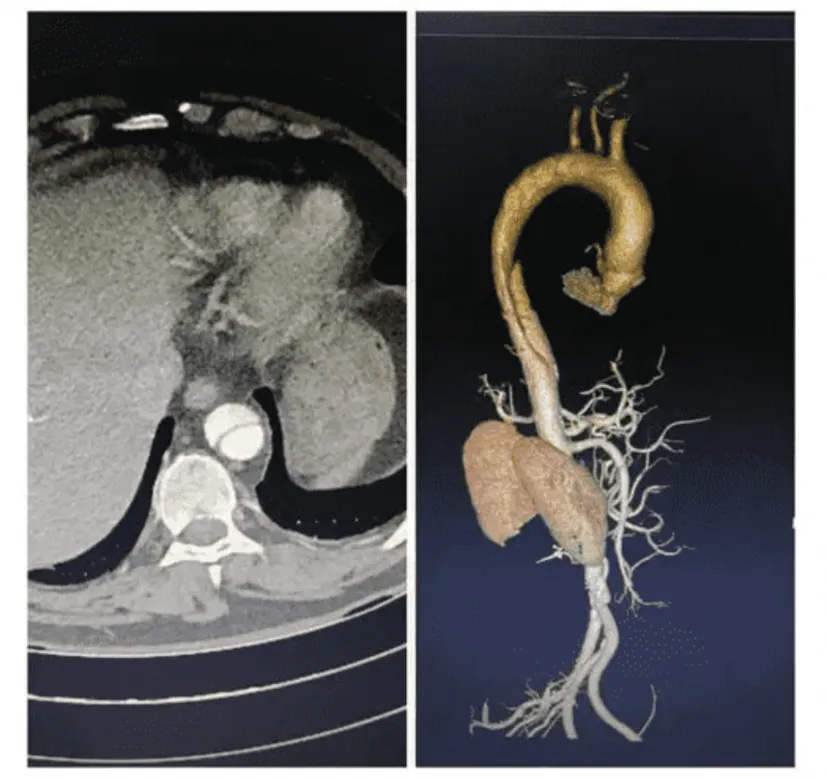

之所以這種疾病這麼恐怖,是因為它的病理機制非常特殊。主動脈本身是人體最大的動脈,而且直接連着心臟,把心臟跳動泵出的血液送到全身。

但由於高血壓等原因,動脈的血管壁是會老化的,一旦脆弱的血管內壁被血流撕破,血液會馬上湧入撕裂口,衝進血管壁中層和仍然完整的血管外層中間,像血做的氣球一樣越鼓越大,直到把整條血管都完全堵死。

被堵住的地方,可能是輸血給身體任何地方的動脈,也可能是心臟自己的動脈,因此主動脈夾層很可能會引起中風、心臟病、腎衰竭等各種問題。

主動脈夾層真正恐怖的地方在於,這個充血氣球的外壁已經很脆弱了,沒人知道它什麼時候就會突然爆開,一旦爆開,血液會立刻決堤灌滿整個胸腔,死亡率100%,神仙來了也救不了。

所以主動脈夾層,本質上就是藏在血管裏的定時炸彈,極度危險。

主動脈夾層的早期跡象,可能只是血管壁上幾毫米的密度變化、一點點不規則的腫脹。這種信號極其微弱,在CT的灰度圖像裏就像一滴水融入了大海,人眼幾乎無法察覺。而這,恰恰是AI的強項。

為了讓 AI 能準確看到CT上的病灶部位,醫生們得先在數據庫裏每一份清晰的增強CT上,像繡花一樣,一筆一筆畫出血管的輪廓,然後,再用算法把這些標準答案跟模糊的平掃CT來對齊,最後AI才能學會離開增強CT,只靠平掃CT就預測出主動脈血管是不是有問題。